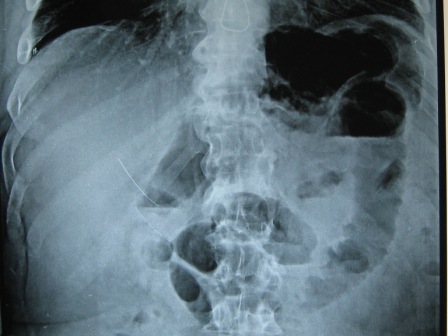

This report is about two cases of acute abdomen-like symptoms that proved to be due to swine flu. Two patients above 60 years of age, with cardiac and respiratory chronic disease, presented with acute abdominal pain. One of them was subjected to abdominal exploration that revealed functional colonic obstruction. The diagnosis of H1N1 was made later upon development of respiratory symptoms. In the other case the diagnosis of H1N1 was made preoperatively, and conservative management was pursued. Once H1N1 was suspected, viral culture was performed and found positive. Acute abdominal symptoms were relieved in both cases by administration of Oseltamivir. Acute abdomen-like presentation of H1N1 Influenza is rare. Suspecting such a diagnosis is crucial to save patients with an H1N1 Acute abdomen-like presentation unnecessary surgery. Cure of the patient and prevention of disease spread depend on accurate diagnosis of H1N1. Surgeons should be aware of the possibility of presentation with acute abdomen-like symptoms, during an H1N1 outbreak.Downloads